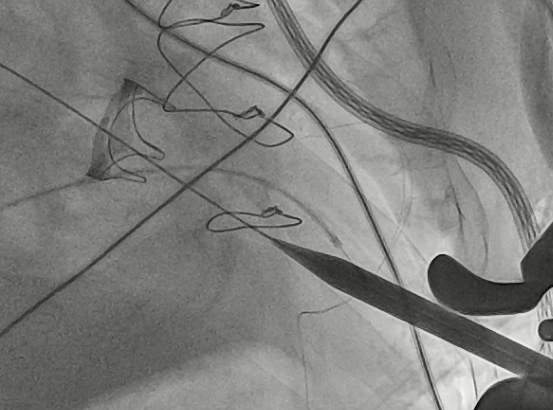

猪尾导管过瓣环平面进左心房

交换加硬导丝

扩张鞘预扩心尖穿刺点

输送器进入左室至生物瓣下方